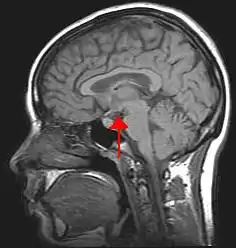

![]() Location of the human hypothalamus | |

The hypothalamus (pl.: hypothalami; from Ancient Greek ὑπό (hupó) 'under', and θάλαμος (thálamos) 'bed') is a part of the brain that contains a number of small nuclei with a variety of functions. One of the most important functions is to link the nervous system to the endocrine system via the pituitary gland. The hypothalamus is located below the thalamus and is part of the limbic system.[1] In the terminology of neuroanatomy, it forms the ventral part of the diencephalon. All vertebrate brains contain a hypothalamus.[2] In humans, it is the size of an almond.